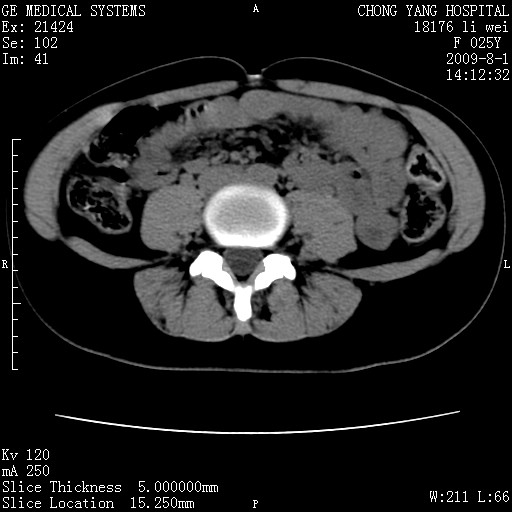

以下是引用pujunzhi在2009-8-1 20:23:00的发言:[br]胸椎旁及背部肌间良性病变,范围广,边界清,沿肌间生长,考虑淋巴管瘤、血管瘤,建议增强扫描。

以下是引用拾荒者在2009-12-30 21:45:00的发言:[br]ct21383:神经纤维瘤病( nf) [br] [br] 神经纤维瘤病。四肢都有,影响美观,四肢上的手术了。[br] [br] [br]谢谢!